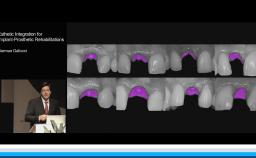

German Gallucci

Boston, United States